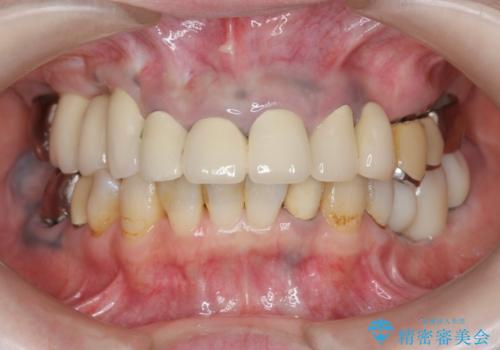

全顎的 虫歯治療 インプラント補綴

- 「他院で虫歯治療を行っているが、延々終わらず数年経過している。全体的な治療を希望したい。」と全顎的な治療を希望され来院されました。

・再発した虫歯

・銀歯の下にできた虫歯

・根尖性歯周炎

・残根状態の歯

など、虫歯を原因とする問題が多発した状態です。

今後延々と治療を繰り返さないために、全ての銀歯を外し虫歯を丁寧に取り切り、根管治療を行い、残せない歯は抜去を行った上でインプラント治療を行っていくことで全体的な治療を計画していくこととなりました。

工程数が多かったため治療期間はかかりましたが、しっかりと安定した噛み合わせ、審美的な口腔内環境を達成することができ大変満足していただくことができました。